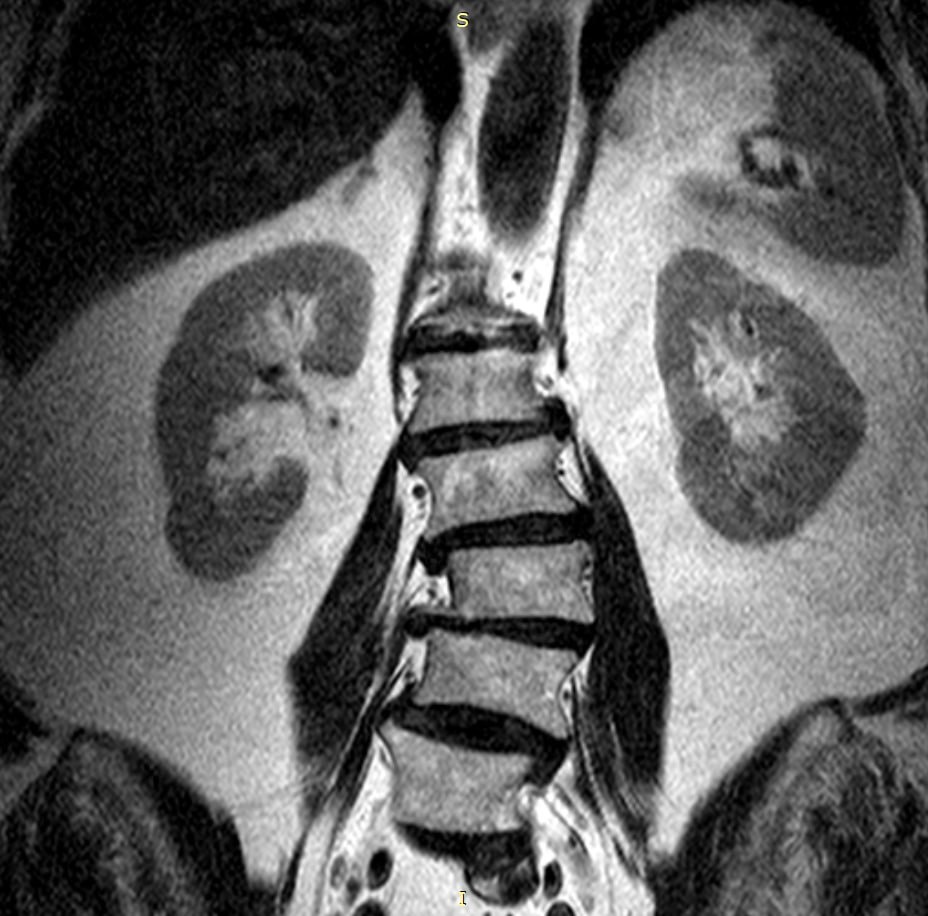

Вот так выглядит "запущенный" позвоночник пациентки 72 лет.

На МРТ видим: множественные грыжи, смещение позвонков, сужение спинномозгового канала, снижение высоты межпозвонковых дисков и костные разрастания. Всё это накапливалось годами.

Вывод простой: проблемы со спиной лучше решать на ранних стадиях. Чем дольше терпеть и откладывать, тем сложнее потом помочь.